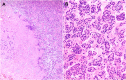

The COVID-19 pandemic has necessitated increased use of telemedicine for diagnosis and management of musculoskeletal disorders. We describe the virtual/telemedicine encounter and management of a patient with knee pain initially diagnosed as gonarthrosis but that actually resulted from an impending pathologic fracture of the femur. Definitive diagnosis and treatment occurred only after completion of the impending fracture. The multiple factors making telemedicine encounters challenging which contributed to this outcome are highlighted. Orthopedists need awareness of these challenges and must take steps to mitigate the risk of complications possible with continued increased utilization of telemedicine during this pandemic and beyond.